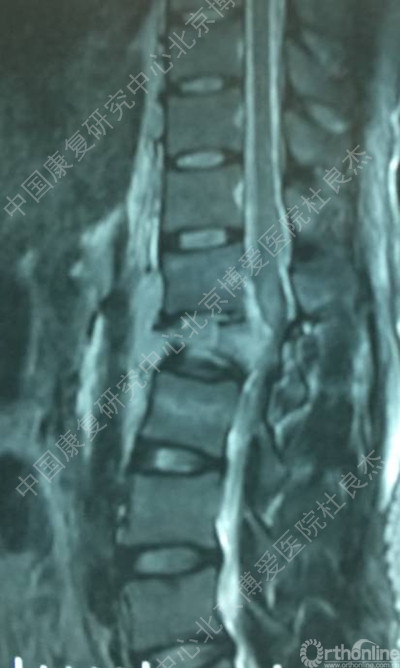

MRI图像